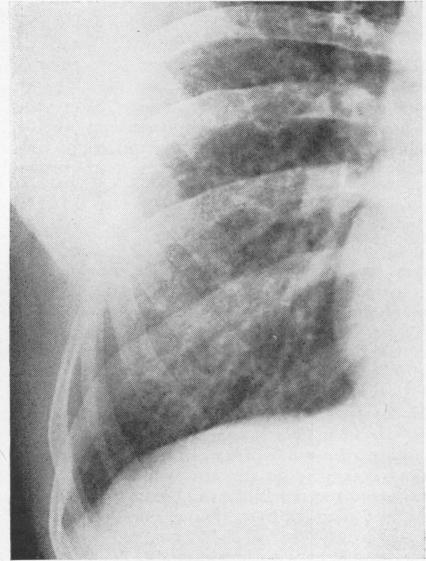

An epidemiological and environmental survey of 170 bagasse workers employed by a raw sugar producing company in Trinidad was carried out in order to assess the prevalence of respiratory symptoms and to determine if exposure to bagasse was associated with alterations in ventilatory capacity. The epidemiological survey failed to reveal a significantly increased prevalence of respiratory symptoms in the more exposed group but showed that the group of Indian workers who were regularly and continuously exposed to bagasse had a significantly lower ventilatory capacity than the control group. This diminished ventilatory capacity was demonstrated despite negligible dust concentrations in the plant. However, the possibility that persistent exposure to low concentrations of bagasse may be the cause must be considered. During a five-year period, 17 patients with bagassosis were seen, the clinical picture being similar to that described in extrinsic allergic alveolitis from other causes. The systematic variations demonstrated in some indices of ventilatory function in different racial groups are discussed.

为评估呼吸道症状的患病率,并确定接触甘蔗渣是否与通气能力改变有关,对特立尼达一家原糖生产公司雇佣的170名甘蔗渣工人进行了一项流行病学和环境调查。流行病学调查未能发现暴露程度较高组的呼吸道症状患病率显著增加,但显示经常持续接触甘蔗渣的印度工人组的通气能力明显低于对照组。尽管工厂内粉尘浓度可忽略不计,但仍显示出通气能力下降。然而,必须考虑长期接触低浓度甘蔗渣可能是原因这一可能性。在五年期间,共诊治了17例甘蔗渣肺患者,其临床表现与其他原因引起的外源性过敏性肺泡炎相似。文中讨论了不同种族群体通气功能某些指标中表现出的系统性差异。